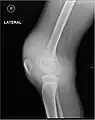

Hémarthrose

L'hémarthrose est un épanchement de sang dans une cavité articulaire consécutif d'une lésion ligamentaire, d'une fracture osseuse ou encore d'une atteinte du cartilage osseux[1]. Cette physiopathologie est caractéristique des personnes atteintes d'hémophilie sévère et dans une moindre mesure chez les formes modérées, car chez les hémophiles, l’absence ou l’altération d’un des facteurs de la coagulation (VIII ou IX selon le type d’hémophilie) perturbe le processus de la coagulation, au point qu’un traumatisme minime peut provoquer un saignement prolongé[2]

Près d'un quart des lésions sévères des ligaments et des genoux capsulaires entraînant une hémarthrose sont associées à des lésions cartilagineuses pouvant mener à une arthrite dégénérative progressive.